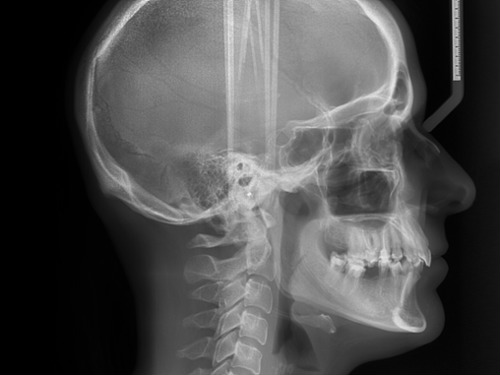

Cephalometric X-Ray

A cephalometric x-ray captures a side-view image of the head and jaw, helping us evaluate facial structure, jaw alignment, and airway space. This imaging is especially helpful when planning orthodontic treatment or assessing airway concerns.